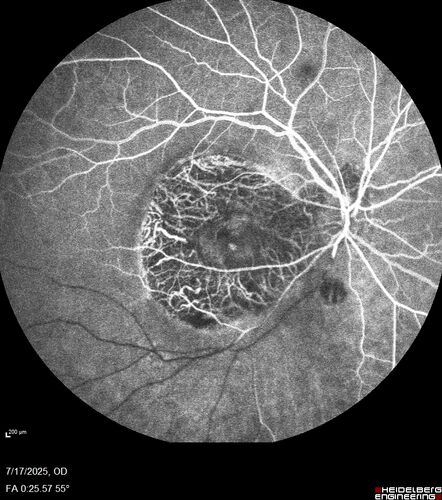

BRAO - plaques in vessels - GIF video of FA

78 year old female with vision loss for 1 week and old macular scar. Images show BRAO with plaques and FA shows occlusion.